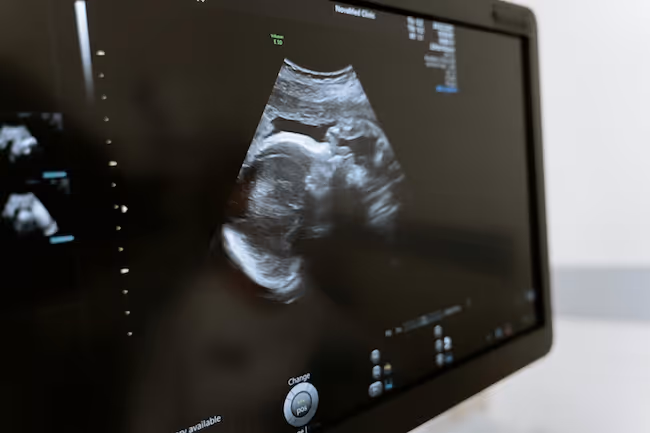

Obstetric Ultrasound Annotation

Landmark and region labeling across fetal views

We annotate fetal measurements, anatomical regions, and structures relevant to obstetric workflows and biometric assessment.